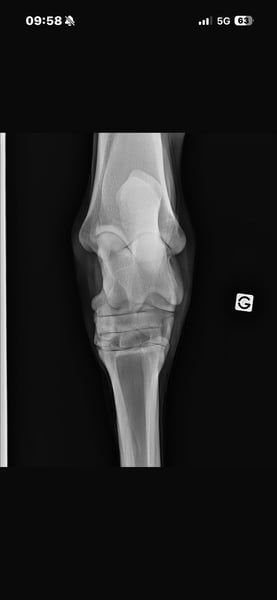

Radios dispos ! En ordre de tout !